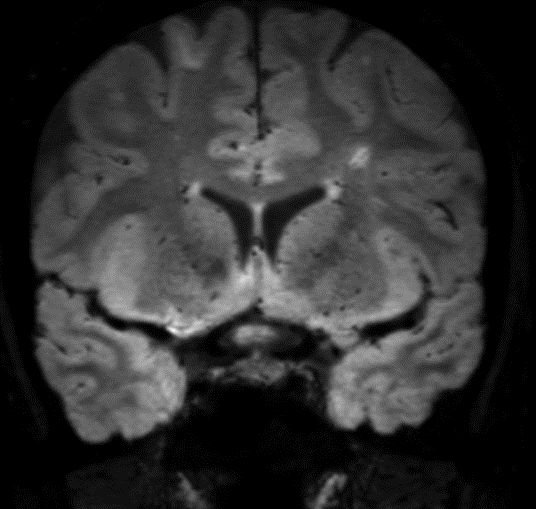

SWI sequence has a high sensitivity to enhance contrast for deoxygenated (venous) blood or calcium deposits. This may help, when used in combination with other clinical information, in the diagnosis of various neurological pathologies. 3D imaging lets you acquire high resolution data in multiple directions in one scan. Isotropic voxel size enables reformats in any plane without loss of resolution. FLAIR* requires offline post processing combining the contrast of 3D FLAIR and 3D SWI EPI into a single image. This enables the visualization of Central Vein Sign, mapping subcortical veins onto 3D FLAIR contrast images.